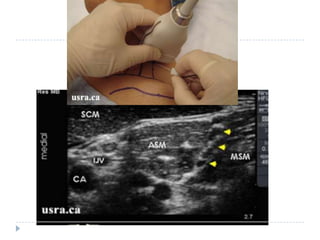

   Riesgo de bloqueos fallidos es 1.62 veces mayor.

   Existe mayor probabilidad de complicaciones asociados

a la anestesia regional.

   Precaución con neuropatías periféricas post – cx.

   Idealmente deben ser colocados por anestesiólogos

entrenados y bajo guía ecográfica.